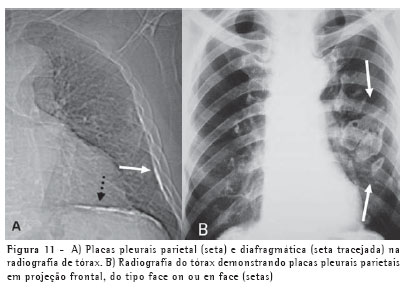

As placas pleurais são a manifestação mais comum da exposição ao asbesto, sendo consideradas marcadores de exposição. Envolvem mais comumente as porções posteriores e laterais da pleura da parede torácica, entre a sexta e a décima costelas, e a pleura diafragmática, principalmente na sua porção superior. A maior parte ocorre na ausência de asbestose e raramente detecta-se asbestose quando placas pleurais não estão presentes. A radiografia do tórax é até hoje o método de imagem mais utilizado na avaliação das placas pleurais (Figura 11).(8-9)

A TCAR é um método mais sensível e específico do que a radiografia. As placas pleurais são caracterizadas na TCAR como espessamentos pleurais focais, geralmente bilaterais, descontínuos, com bordas lisas, em platô, e por vezes com calcificações (Figura 12).(10-11)